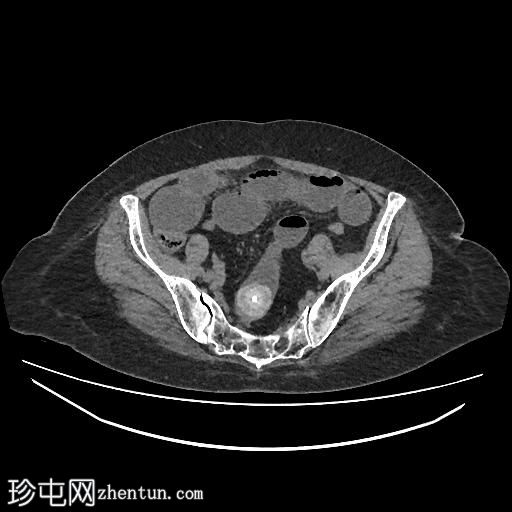

矢状位增强扫描(门静脉期)

胆囊缩小,囊壁增厚,提示慢性炎症改变。胆囊(底部)与十二指肠(球部)腔之间可见细小瘘管,胆囊内及肝内、肝外胆管内均可见气体(胆道积气)。

远端空肠内嵌顿一枚较大的胆结石(3.5 cm),近端空肠袢扩张,回肠袢、末端回肠及结肠均塌陷。